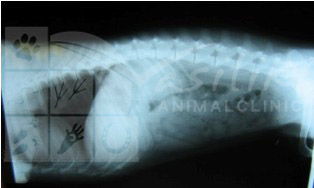

Apart from the radiography performed for diagnostic purposes of pathological conditions, in our clinic we perform examination and radiographic imaging for early detection of hereditary/genetic conditions such as HIP DYSPLASIA, ELBOW DYSPLASIA etc. of large breed dogs.